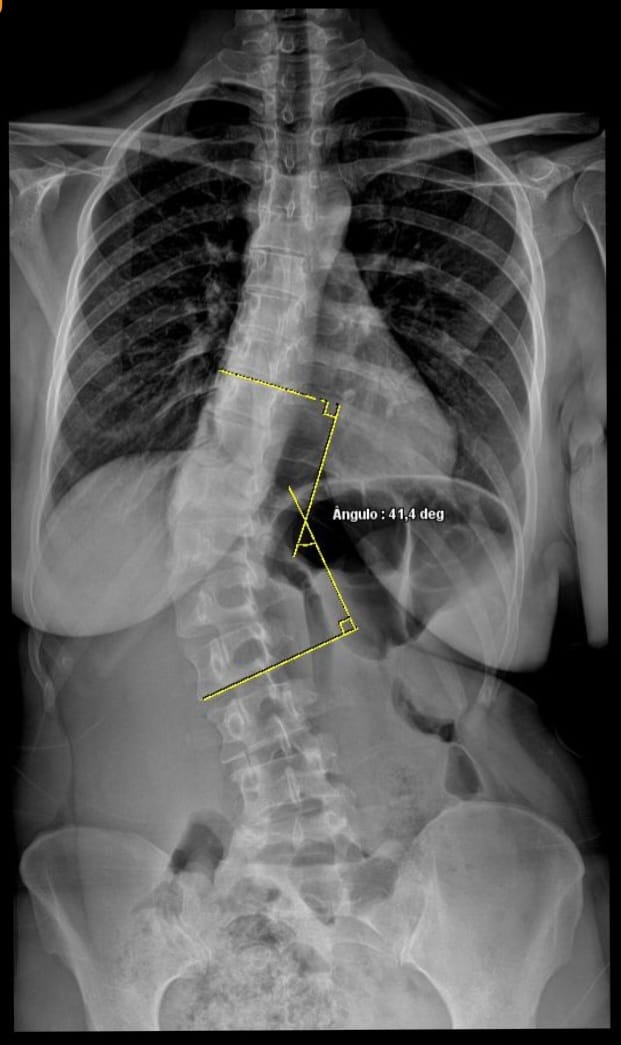

HSJ conta com atendimento de Raio-X completo de coluna para tratamento de escoliose

O HSJ agora conta com atendimento completo de Raio-X de coluna, auxiliando no diagnóstico e acompanhamento da escoliose com mais precisão e qualidade.

Com exames mais complexos e tecnologia avançada, o hospital amplia seus serviços para oferecer mais segurança, agilidade e cuidado para pacientes de Maravilha e toda a região.